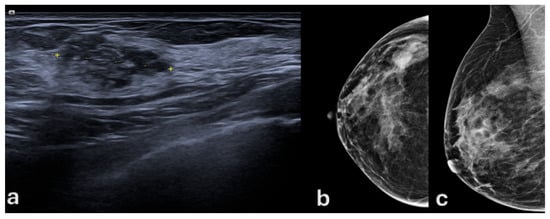

- Chiang, C.-L.; Liang, H.-L.; Chou, C.-P.; Huang, J.-S.; Yang, T.-L.; Chou, Y.-H.; Pan, H.-B. Easily recognizable sonographic patterns of ductal carcinoma in situ of the breast. J. Chin. Med. Assoc. 2016, 79, 493–499. [Google Scholar] [CrossRef][Green Version]

- Uematsu, T. Non-mass lesions on breast ultrasound: Why does not the ACR BI-RADS breast ultrasound lexicon add the terminology? J. Med. Ultrason. (2001) 2023, 50, 341–346. [Google Scholar] [CrossRef]